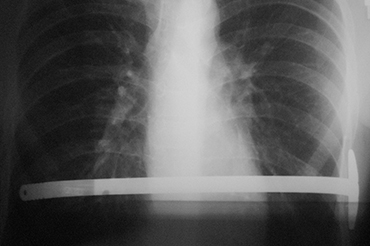

Pectus Excavatum

Adolescentes